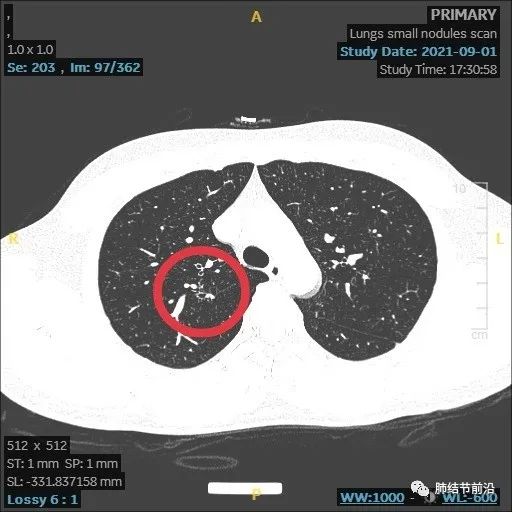

患者之后再复查,果然结节大部分吸收。

本病例显示了炎症性结节的发展过程,由8mm实性结节,变成了14mm的多中心堆积结节,后面又自行吸收。炎症为何种病菌感染,无法肯定,该结节也有结核可能。

多中心堆积结节,多考虑炎症肉芽肿,如果病灶中随访慢慢变实性,再考虑为腺癌。应注意影像特点,避免误切。